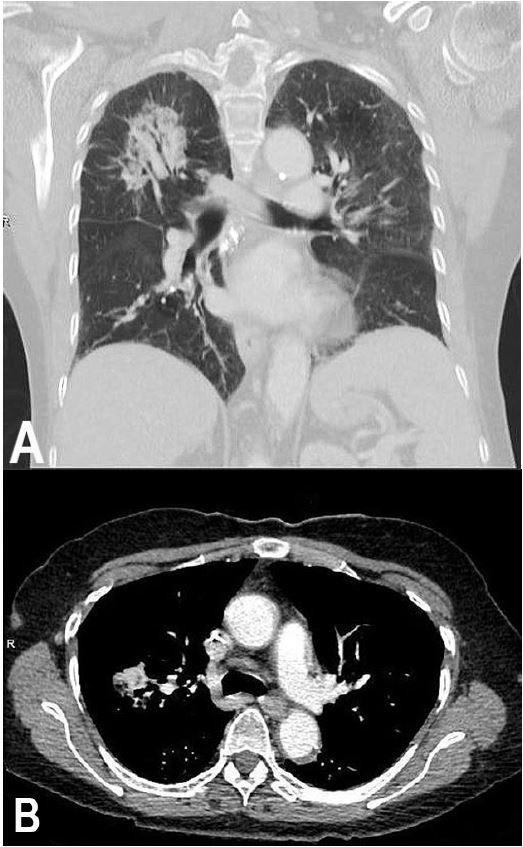

Pulmonary placental transmogrification (PT) is a rare entity with less than 40 cases reported in the literature. Most reported cases are associated with either bullous emphysema or with pulmonary fibrochondromatous hamartomas. We present only the second case of PT associated with adenocarcinoma of the lung. A 67-year-old female with multiple chronic medical ailments presented with shortness of breath and was found to have a 6-cm mass in the upper lobe of her right lung. A computed tomography (CT) guided core biopsy was performed that showed a well-differentiated adenocarcinoma. Interestingly the normal lung tissue showed placental villous architecture. A unique feature of our case is that the diagnosis was made on a needle core biopsy, unlike all the other cases in the literature. We also provide a comprehensive review of this rare entity.

肺胎盘化生(PT)是一种罕见的疾病,文献报道的病例不足40例。大多数报道的病例与大疱性肺气肿或肺纤维软骨瘤性错构瘤有关。我们仅报告第二例与肺腺癌相关的PT。一名患有多种慢性疾病的67岁女性因呼吸急促就诊,发现右肺上叶有一个6厘米的肿块。进行了计算机断层扫描(CT)引导下的芯针活检,结果显示为高分化腺癌。有趣的是,正常肺组织显示出胎盘绒毛结构。我们病例的一个独特之处在于,与文献中的所有其他病例不同,该诊断是通过针芯活检做出的。我们还对这种罕见疾病进行了全面综述。